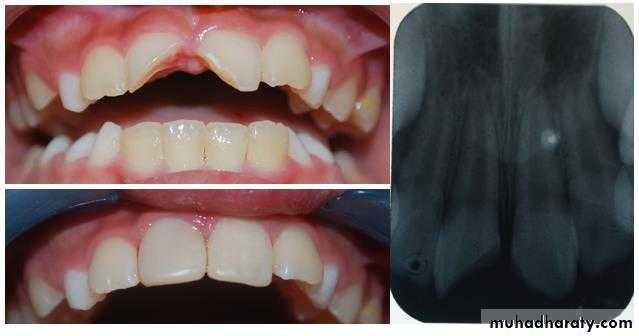

DefinitionThe procedure in which the small exposure of the pulp, encountered during cavity preparation or following a traumatic injuries or due to caries, with a sound surrounding dentin, is dressed with an appropriate biocompatible radiopaque base in contact with exposed pulp tissue prior to placing a restoration.

Small pin point mechanical pulp exposure of diameter less than 1mm .Traumatic exposure in a dry , clean field which reported to the dental office within 24 hours ( without previous symptoms of pulpitis with normal radiographical finding ) .

Small pin point pulp exposure= 1mm